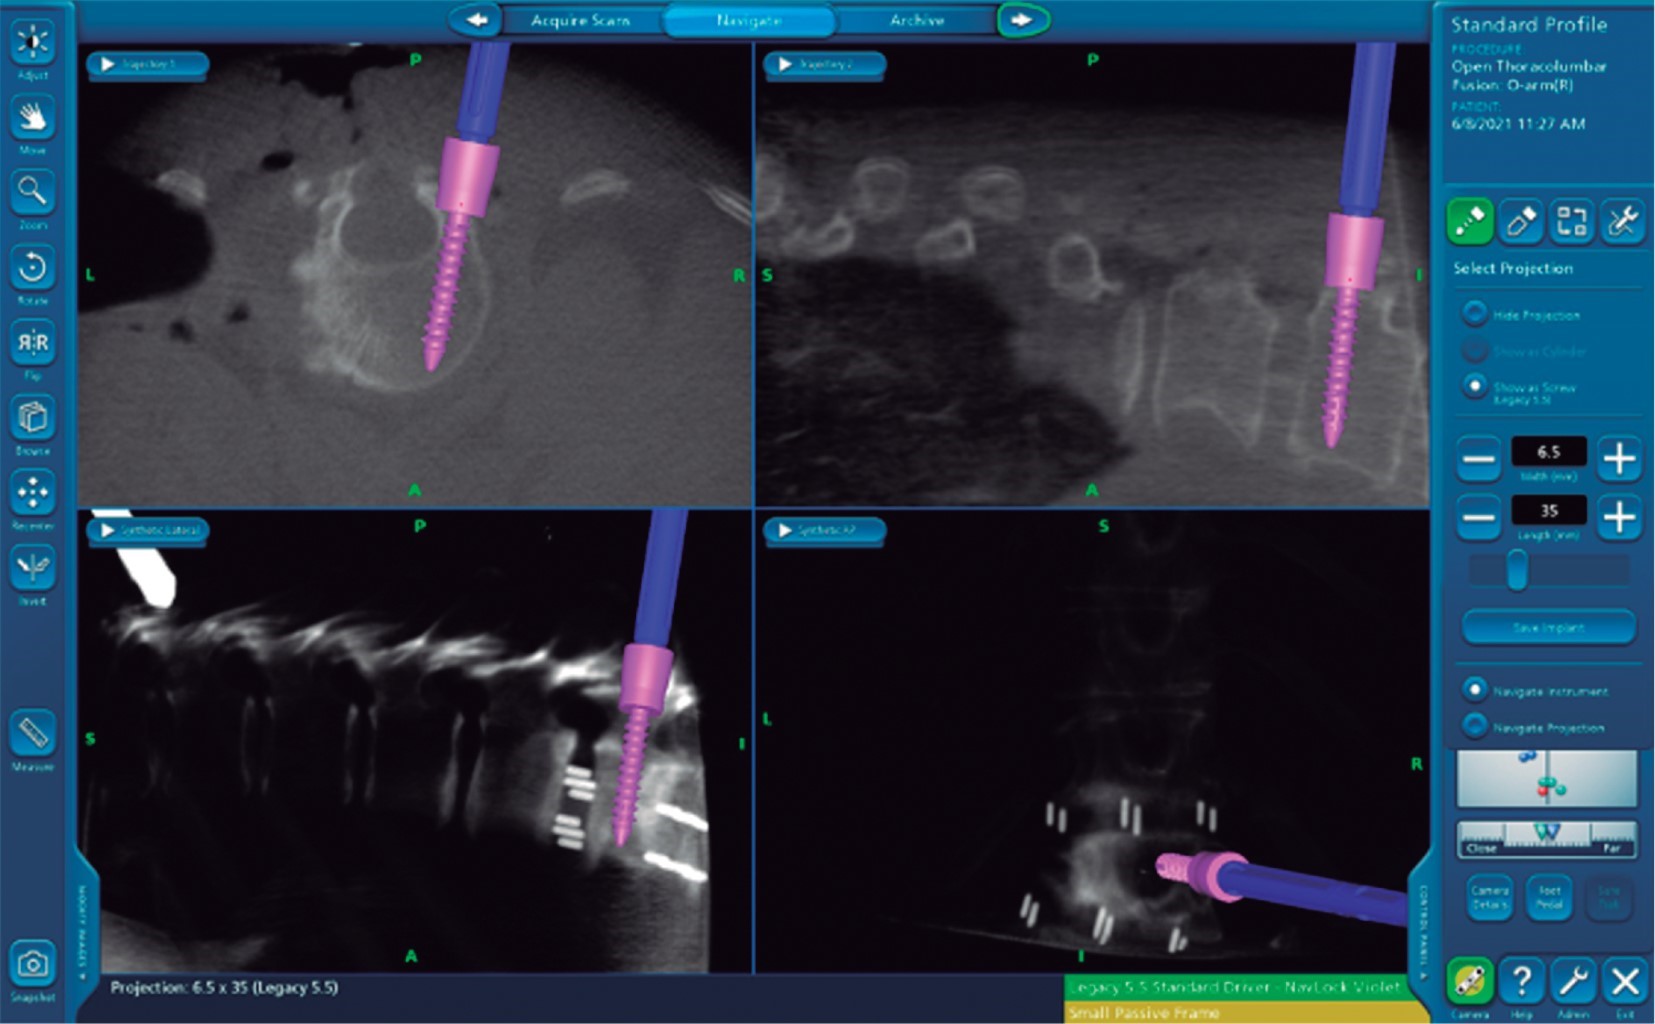

Tratamiento: corrección de escoliosis, mixta XLIF T12 a L4, tornillos pediculares de T9-S1 con navegación O-ARM & StealthStation, (TLIF) de L5-S1 y fusión posterolateral (Figuras 5 y 6).

El uso de O-ARM disminuye prácticamente la exposición a radiación al personal médico y de la sala de quirófano, ya que se realiza un único barrido abarcando cinco segmentos por barrido, lo cual conlleva una radiación de 10 Msv.9 El uso de C-ARM nos da fallas hasta de 20% con rupturas de pedículo mayores a 4 mm en 3.8% de los casos detectados con TAC posterior a evento quirúrgico.10 Un 97.5 a 99% de los tornillos colocados con navegación se ponen correctamente (Figura 7).

La asociación de O-ARM con lesión nerviosa va de 1-3%. Con el uso de C-ARM está estimada la falla de colocación de tornillos en segmentos largos hasta de 41% (G0-G1-G2-G3-G4). Con el O-ARM, el mayor desplazamiento que se espera es un G0-1 < 2 mm.3 Con O-ARM el tiempo estimado de colocación de tornillo es de 2-8 min. A diferencia de C-ARM (15-20 min) en O-ARM (Figuras 8 y 9). Como limitación, existe el costo y la diferencia medida con el punzón del tornillo real 3.14 mm. Se ha reportado que de cada 436 tornillos colocados, sólo existen 4 fallas cuando se unen O-ARM Y NAVEGACION (0.9%), y aun así, demuestra una baja probabilidad de lesión nerviosa al ser colocados como G0-G1 (Figura 10).

Figura 5

Figura 6

Figura 7

Figura 8

Figura 9

Figura 10